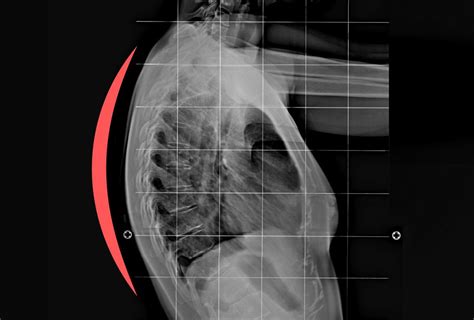

Kyphosis refers to an excessive outward curve of the thoracic spine (the upper and middle back). While a slight natural curve is normal, an exaggerated curve can lead to a “hunchback” appearance, chronic back pain, and restricted movement. Understanding the underlying cause is the first step in determining the path toward correction.

• Scheuermann’s Kyphosis: This structural condition occurs during adolescent growth spurts when the vertebrae grow unevenly. It is more rigid and challenging to correct than postural kyphosis.